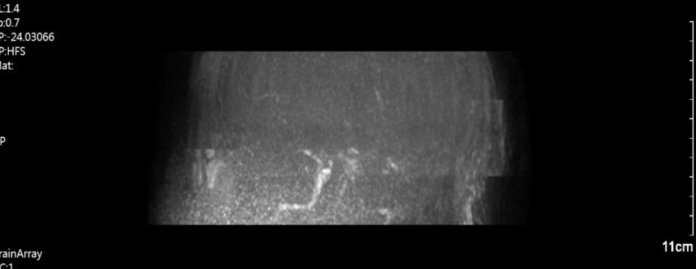

1.DWI示左侧额叶、颞叶及顶叶急性梗死灶。FLAIR示左侧大脑半球未见明显显影。FLAIR及DWI不匹配。

2.MRA示左侧颈内末端以远不显影。

术前MRA